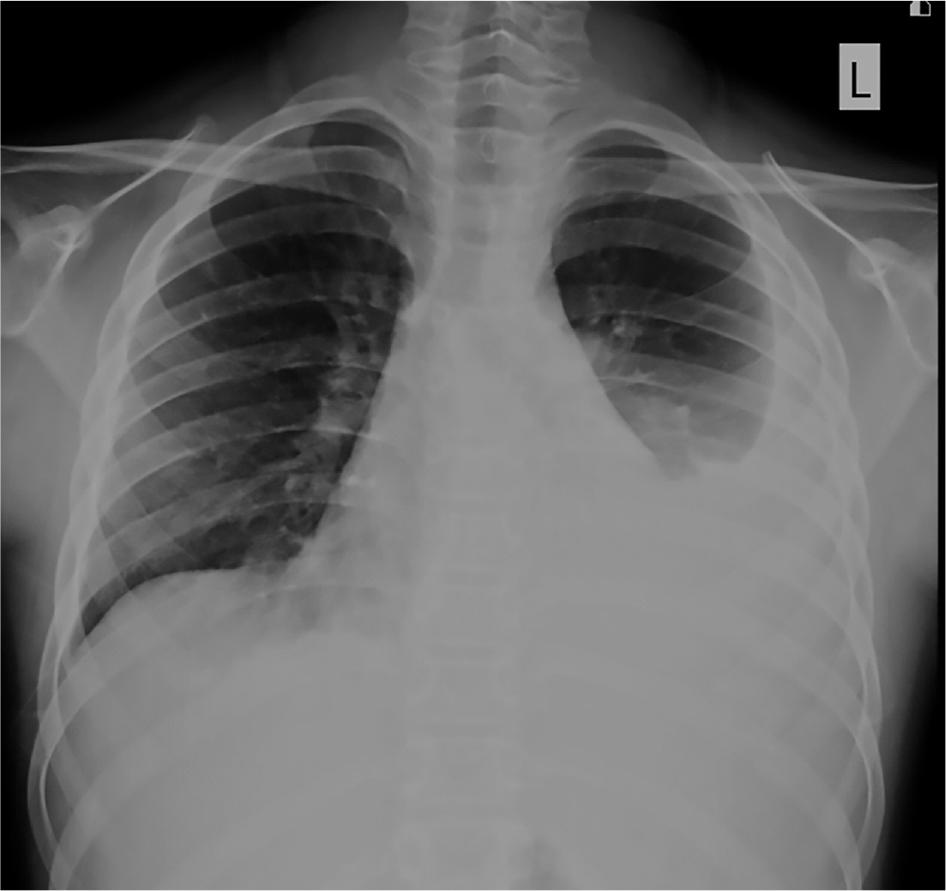

Figure 1